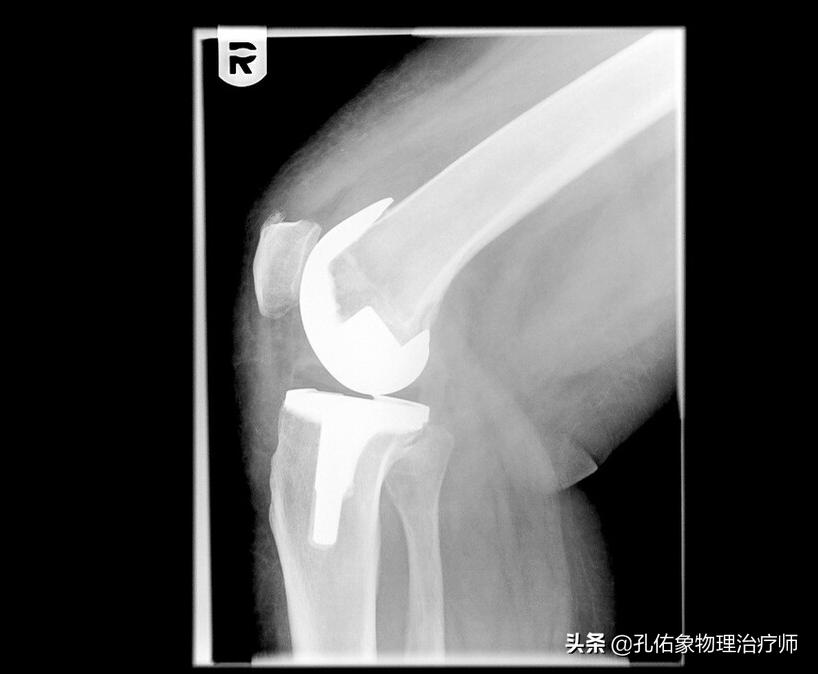

4.若是已经发展到关节炎,说明软骨已经退变很严重,要想再来恢复损伤的软骨,从目前的医疗水平而言,基本不可能。倘若已经严重影响您的生活质量,目前最常见的处理方式是关节置换。